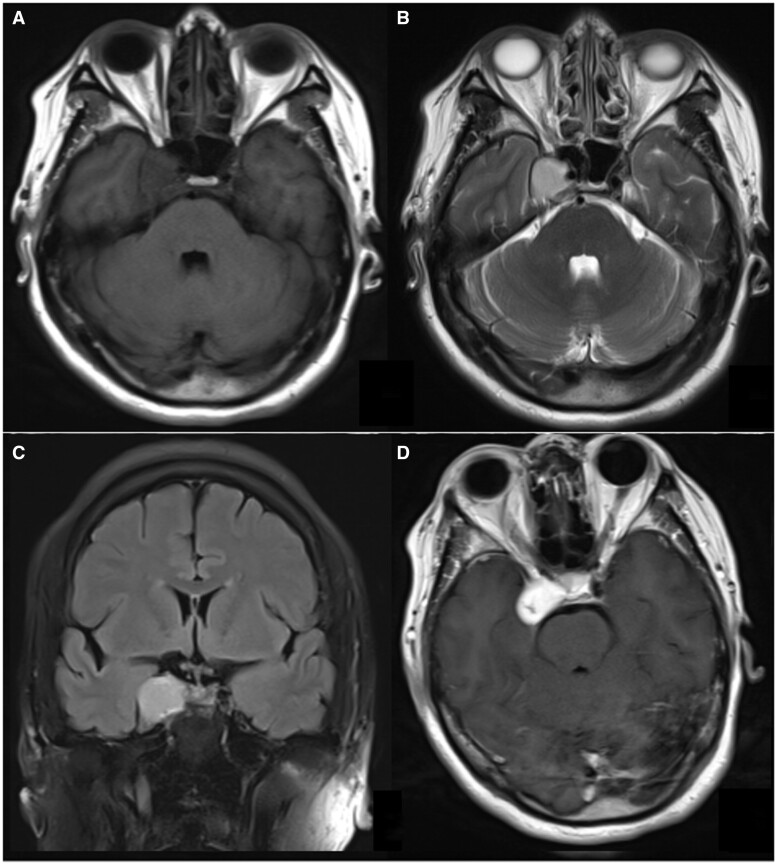

Generally, due to the complexity of the skull base structures, it is difficult to differentiate cavernous vascular malformation and meningioma in the cavernous sinus area using conventional imaging studies. Cavernous sinus venous malformation are characterized by increased capillary masses without a direct arterial supply, typically leading to low perfusion. On the other hand, meningiomas receive arterial blood supply to the tumour and often exhibit high perfusion. So, arterial spin labelling (ASL) can be helpful in distinguishing between the 2 tumour types. However, in our specific case of a cavernous sinus venous malformation, the ASL imaging showed hyperperfusion. Further analysis revealed that this hyperperfusion on ASL can occur when cavernous sinus venous malformation is associated with arteriovenous fistula malformation.